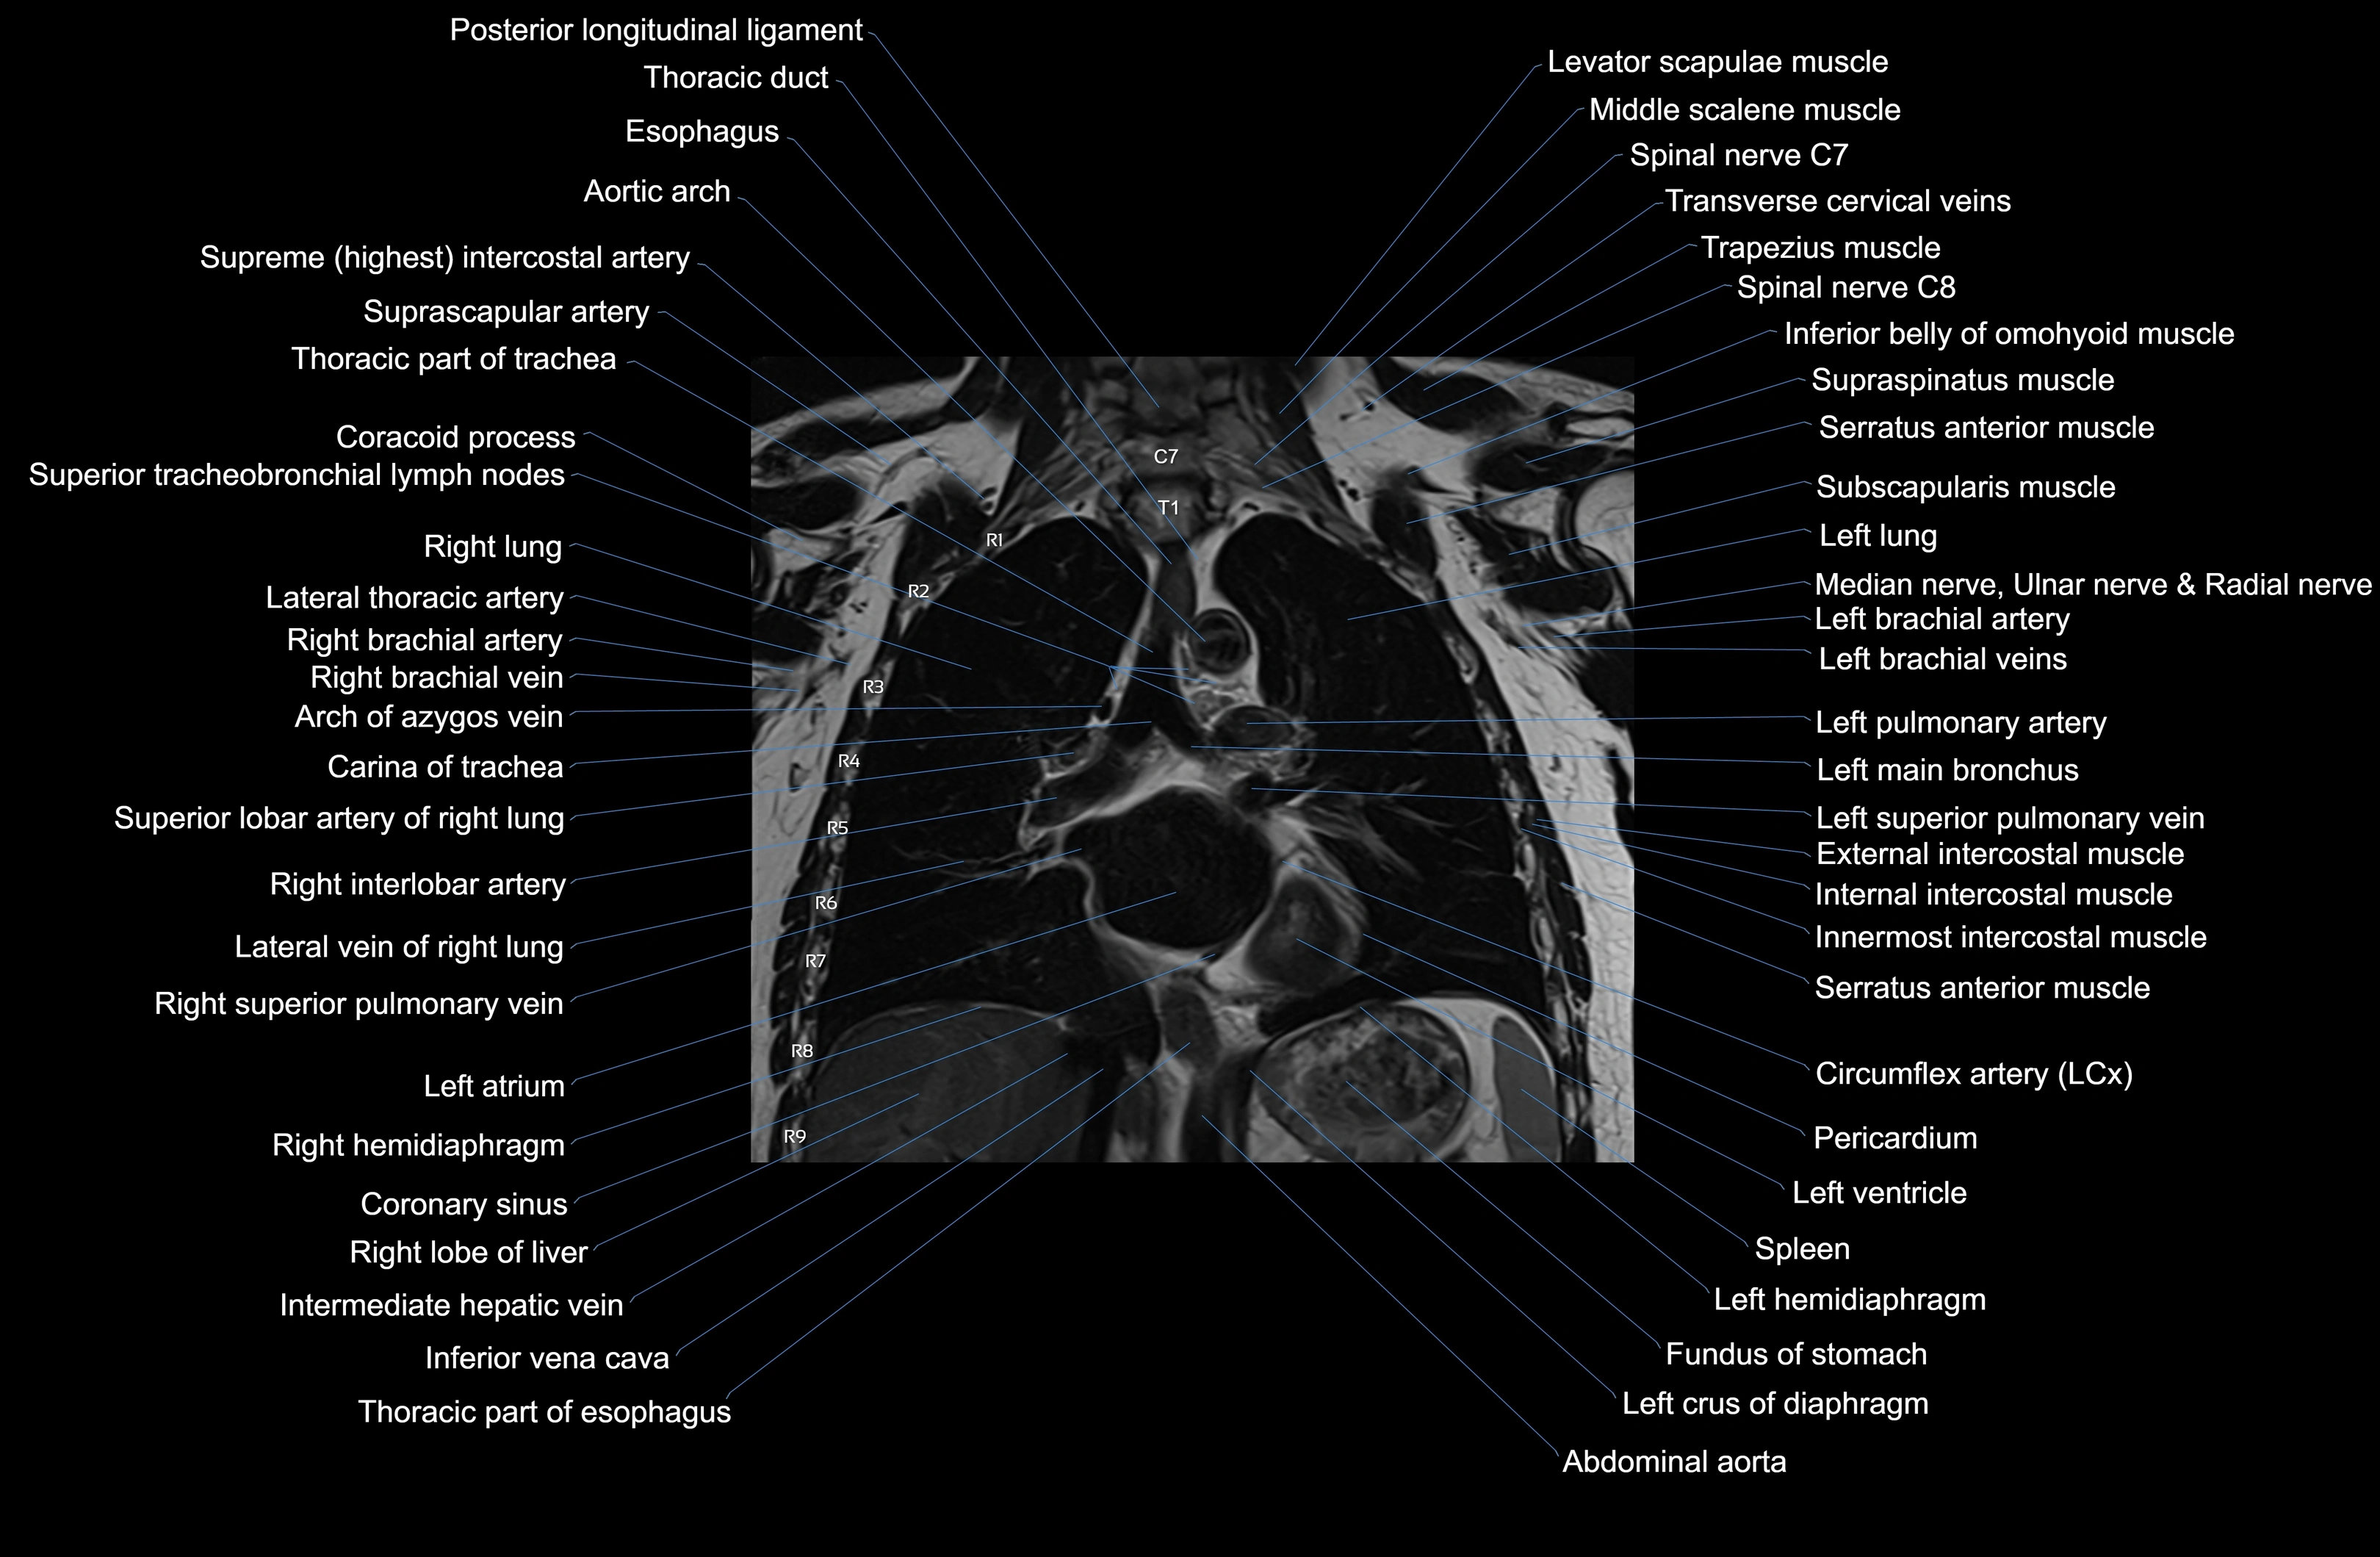

MRI images